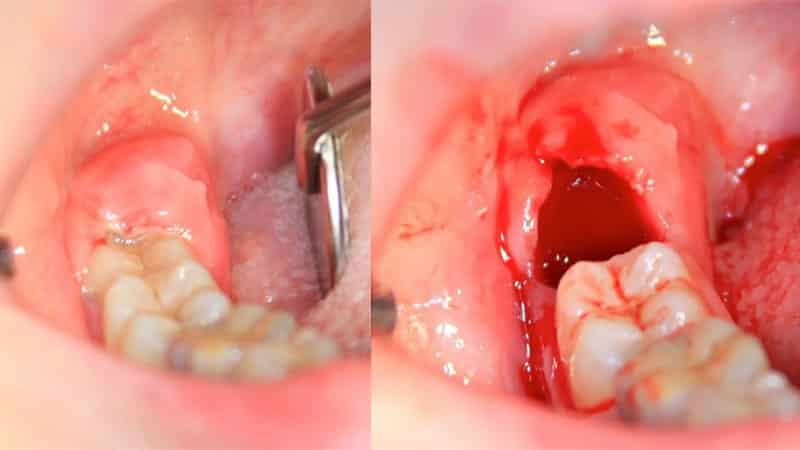

В таких ситуациях хирург-стоматолог проводит более сложные манипуляции. Сначала осуществляется иссечение тканей над зубом и отделение их от кости. Затем зуб аккуратно выпиливается с помощью бормашины до нужного объема и формы, после чего происходит его ампутация.

После удаления зуба и удаления всех осколков лунка обрабатывается антисептиками, и накладывается обеззараживающий компресс.